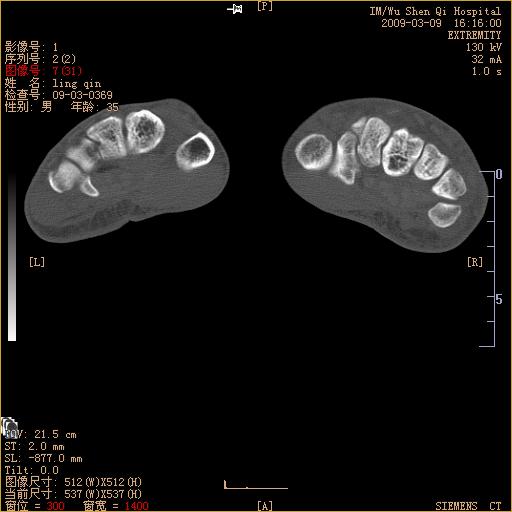

标题: CT18570:右手外伤10余天

左侧舟骨及桡骨茎突骨折,第一掌骨基底部好像也有骨折,建议上传平片